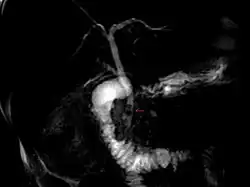

Magnetic resonance cholangiopancreatography (MRCP) image of two gallstones in the distal common bile duct